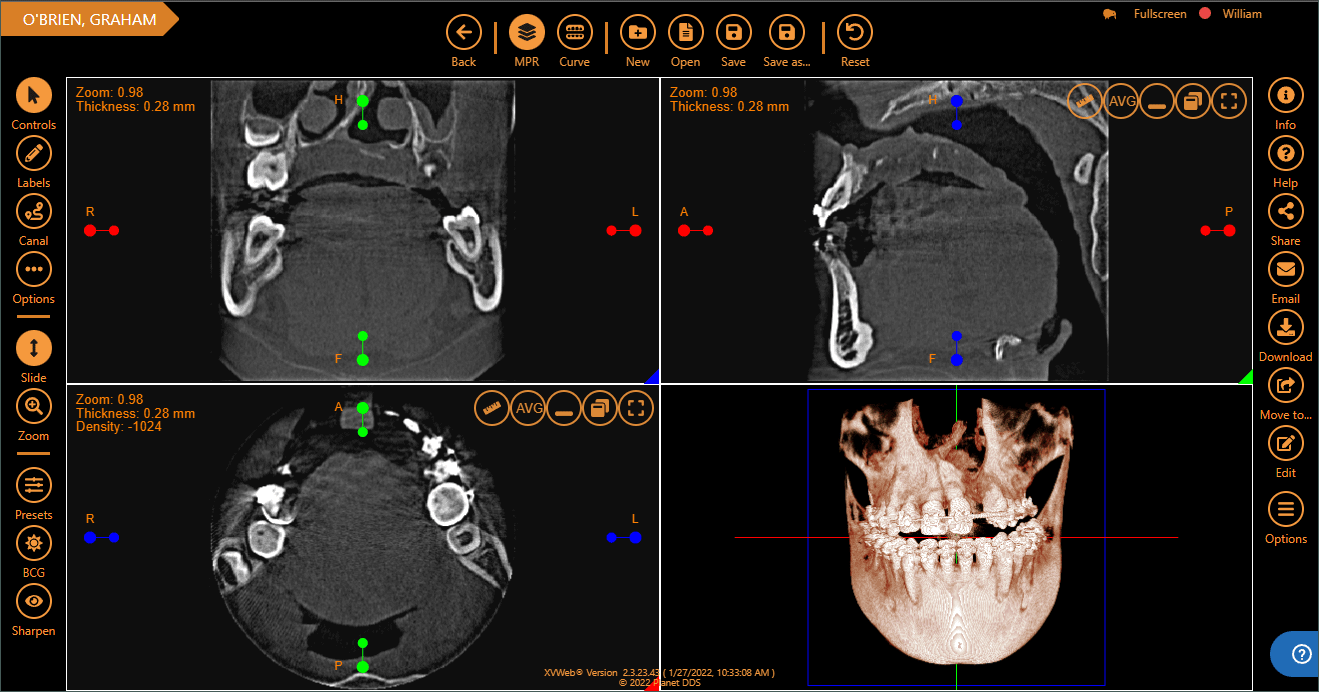

Apteryx XVWeb allows dental professionals to securely capture, store, and access X‑rays from anywhere. Apteryx is dental X-ray software built for practices seeking diagnostic accuracy, consistent imaging, and seamless integration with the devices they already use.

Capture, view, and analyze images in one place, from any device.

Leverage custom clinical filters and image enhancement tools, templates, bitewings, and measurement tools. Quickly detect untreated conditions with AI analysis.

What is Apteryx 3D?